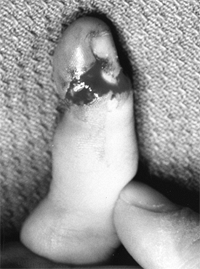

Classification of nerve injury in the ambulatory child has included

II, III, and IV are illustrated (Fig. 23.3).